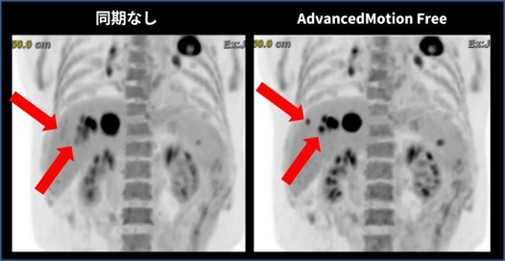

両機種には呼吸同期の機能が搭載されています。Advanced MotionFree (AMF) はGE HealthCareのデバイスレス呼吸同期技術であり、外部デバイスの装着が不要で、特別なセットアップを必要としません。撮影中に装置がリアルタイムで呼吸の影響を解析し、呼吸同期の要/不要を自動的に判定するため、ルーチン検査の流れの中で自然に活用することが可能です。呼吸同期画像では、呼吸の影響を受けやすい横隔膜近傍の集積をより正確に描出できるだけでなく、定量性の向上にも寄与します。図 4の呼吸同期ありの画像では、呼吸同期なしの画像と比較して腫瘍がより明瞭に描出されていることが確認できます。

図 4. 呼吸同期ありとなしの画像比較